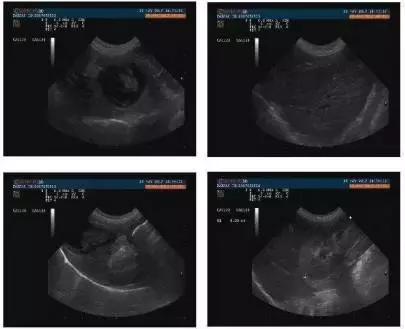

2.4.2 腹部超声

腹部超声检查可见膀胱中等充盈,子宫体直径为0.44cm,胆囊内中等强回声光团,内壁增厚,肾脏皮质回声升高,皮髓分界尚可,十二指肠呈波浪状,远端回声增强。

诊断